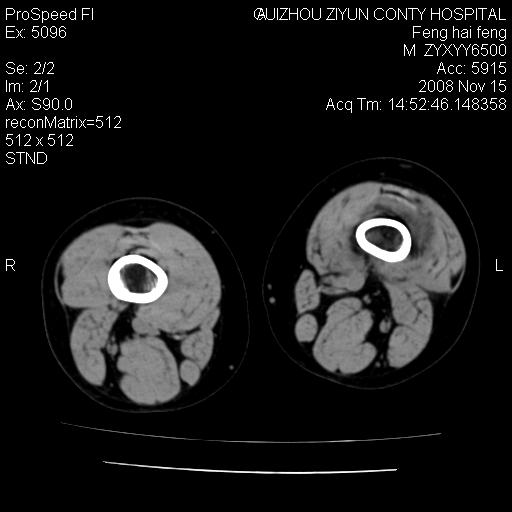

标题: CT16656:M 14Y 左膝关节肿胀一年余。其余病史不详。 [打印本页]

标题: CT16656:M 14Y 左膝关节肿胀一年余。其余病史不详。

考虑左侧髌骨结核;左膝关节滑膜肿胀、增厚,关节囊积液。

左膝滑膜型关节结核可能性大!支持!滑膜型关节结核主要ct表现:关节囊肿胀,积液,关节面见小破坏灶,并见点状死骨!

好大的左腿!考虑左侧髌骨结核,左膝关节滑膜肿胀、增厚,关节囊积液。

左侧髌骨结核;左膝关节滑膜肿胀、增厚,关节囊积液